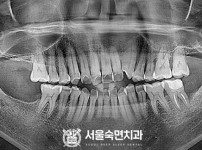

임플란트-전후사진2